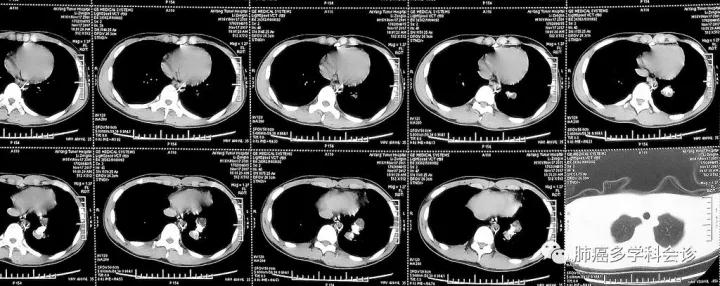

3.  此患者的肺内转移灶几乎完全钙化,也是造成延误诊断的原因之一。下图为另外一位年青骨肉瘤患者肺转移的CT图像,肺占位既有钙化又有软组织成分,不易被误诊。